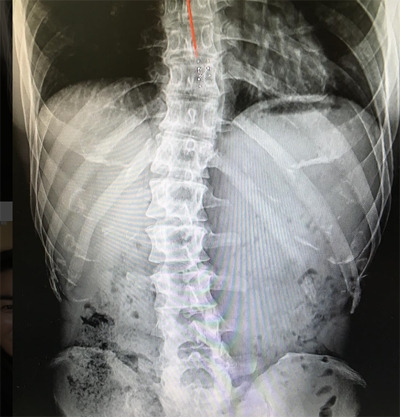

허리디스크 혹은 척추측만증 관련해서는 유전적 영향도 큰 부분이라고 한다.

지금은 허리에 관한 글을 쓰니 허리통증에 관한 예시를 들자면, 앞서 말했듯이 척추측만증이나 허리디스크 관련 해서는 유전적인 요인도 있다.

유전적으로 허리디스크가 발생했거나, 척추측만증이 있는 것이 아니라면 사실 허리가 아픈 것은 결국 신경계나 근골격계의 균형이 파괴되어서 발생하는 문제이다.(너무 광범위한가?)